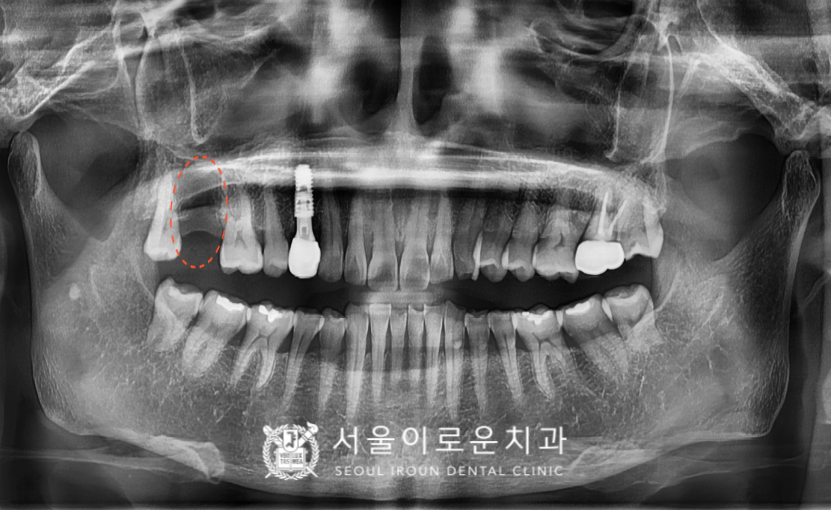

그리고 해당 치아 뿐만 아니라

다른 부위에서도

문제가 있는 부위들을

발견할 수 있었는데요…!

주황색 동그라미 표시의

오른쪽 위 두 번째 큰 어금니(#17)의

기존 보철하였던 치아가

동요도가 심하고, 뿌리까지 염증이

진행된 것을 확인할 수 있었습니다.

환.자분께 설명드렸으나

아직까지 불편감이 없어

좀 더 사용하시길 원하셔서

차후 통증과 같은

증.상이 나타나게 될 경우

발치 후 임플란트 치료 가능성을

설명해 드렸습니다.